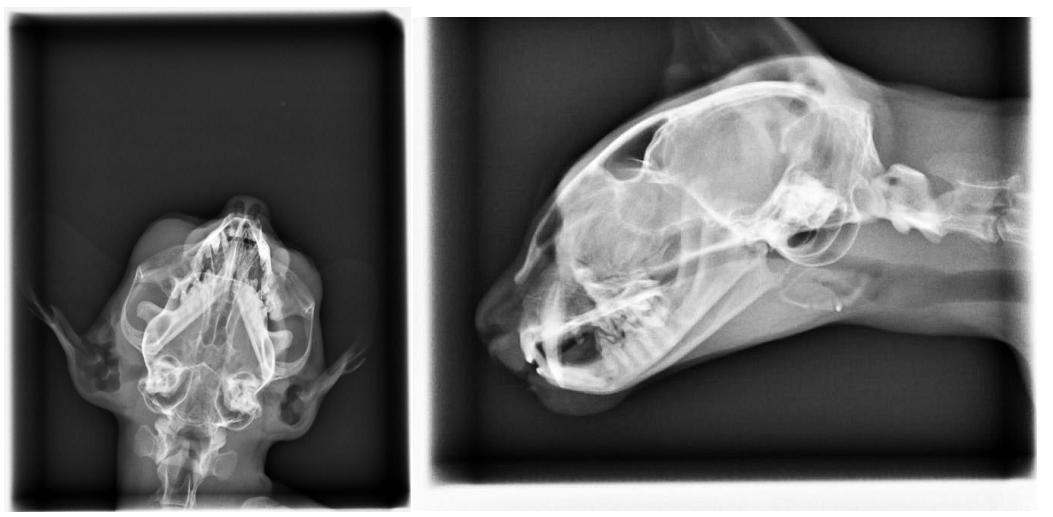

經檢查發現,

貓咪疑似受到撞擊.雙眼縮瞳.神經反應差.有神經症狀

呼吸急促.鼻腔出血

2.X-RAY 400*6